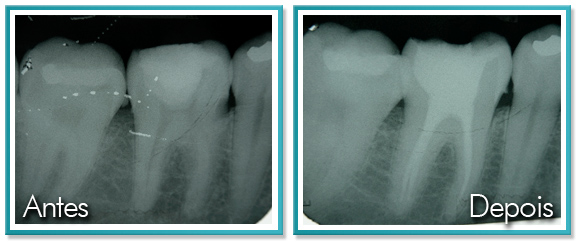

9. AÇÚCAR x CÁRIES

Saiba mais sobre o que é mito e o que é verdade sobre as temidas cáries. Açúcar e Cáries andam sempre juntos. Porém, a quantidade total de açúcar que se consome tem menos impacto na formação de cáries do que a maneira como esse açúcar é consumido. A cárie ocorre quando as bactérias que revestem os dentes se alimentam de açúcares simples. Ela cria um ácido que destrói o esmalte do dente.

Quando se come algo doce, a bactéria leva por volta de 20 segundos para converter o açúcar em ácido, que então dura por 30 minutos. Isso significa dizer que uma lata de refrigerante é bem menos prejudicial do que chupar balas, por exemplo, pois balas e chicletes são consumidos várias vezes durante o dia e expõem o dente à ação dos açúcares mais vezes.

Os fatores que vão aumentar o risco de cárie não incluem a quantidade total de açúcar, mas o padrão de consumo. Você é do tipo que está constantemente dando goles? Costuma tomar doses de café diversas vezes durante o dia?

Conclusão: Pequenas quantidades de açúcar consumidas frequentemente aumentam a incidência de cáries mais do que grandes quantidades de açúcar consumidas com menos frequência.